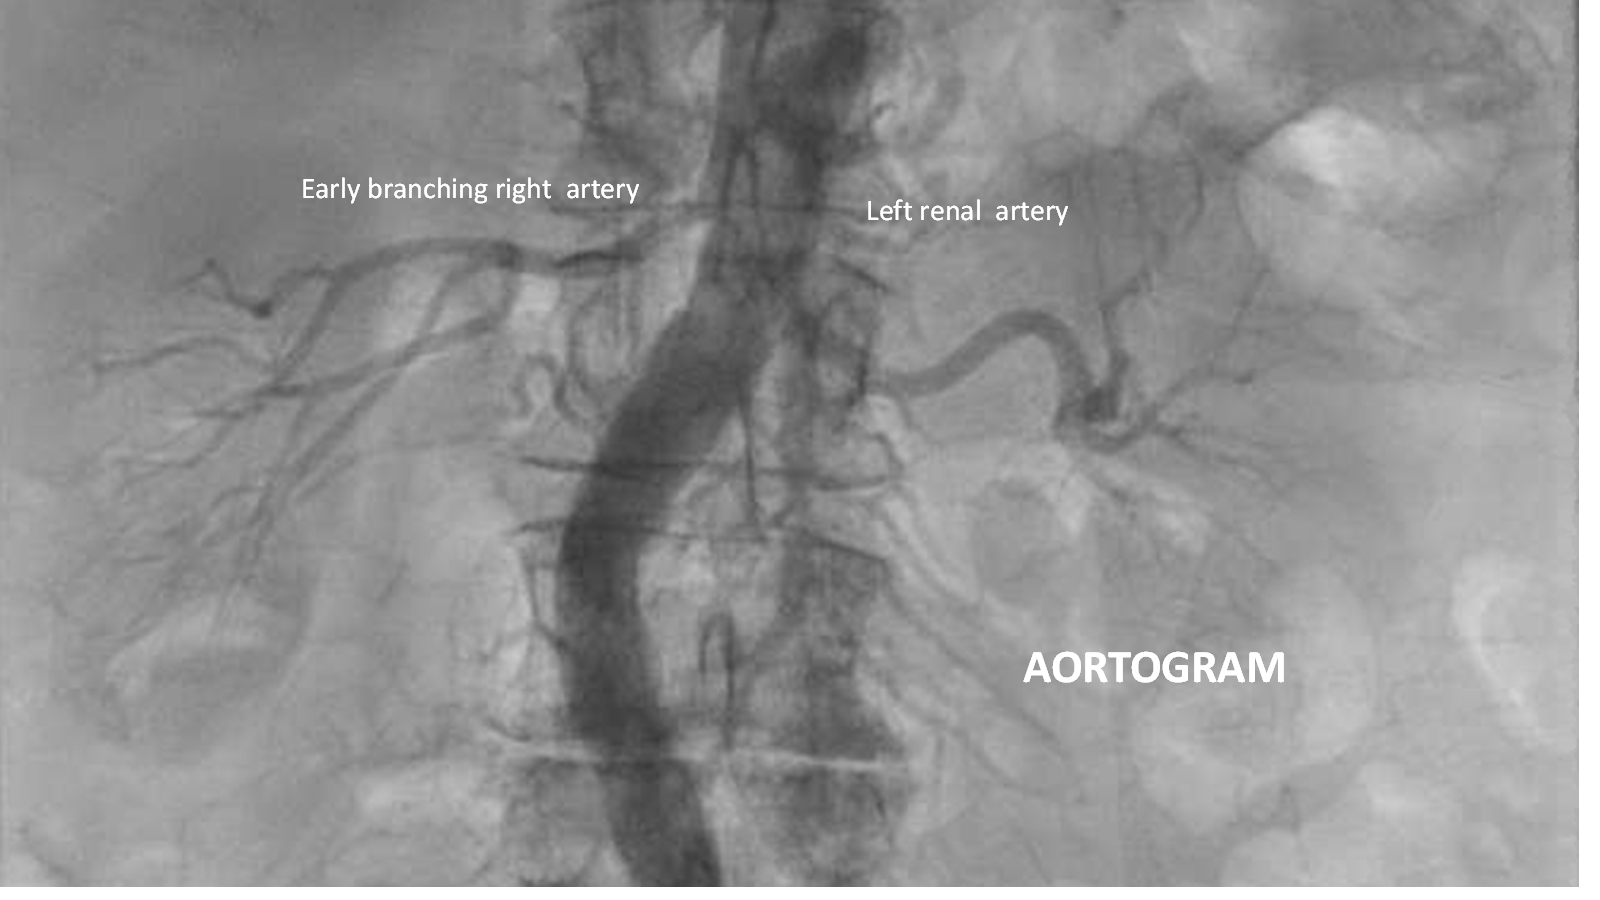

• Access and Angiography: A 5 French Omni Flush catheter (Angiodynamics) was introduced via femoral access over an .035-inch J-tipped wire, and an aortogram confirmed patent bilateral renal arteries without stenosis.

• Renal Anatomy Assessment: The right renal artery exhibited early bifurcation, while the left renal artery was long.

• Renal Artery Imaging: A 5 French pigtail catheter was used for nonselective aortography, confirming single renal arteries bilaterally with a bifurcation on the right side. No significant abnormalities were noted in the renal parenchyma.